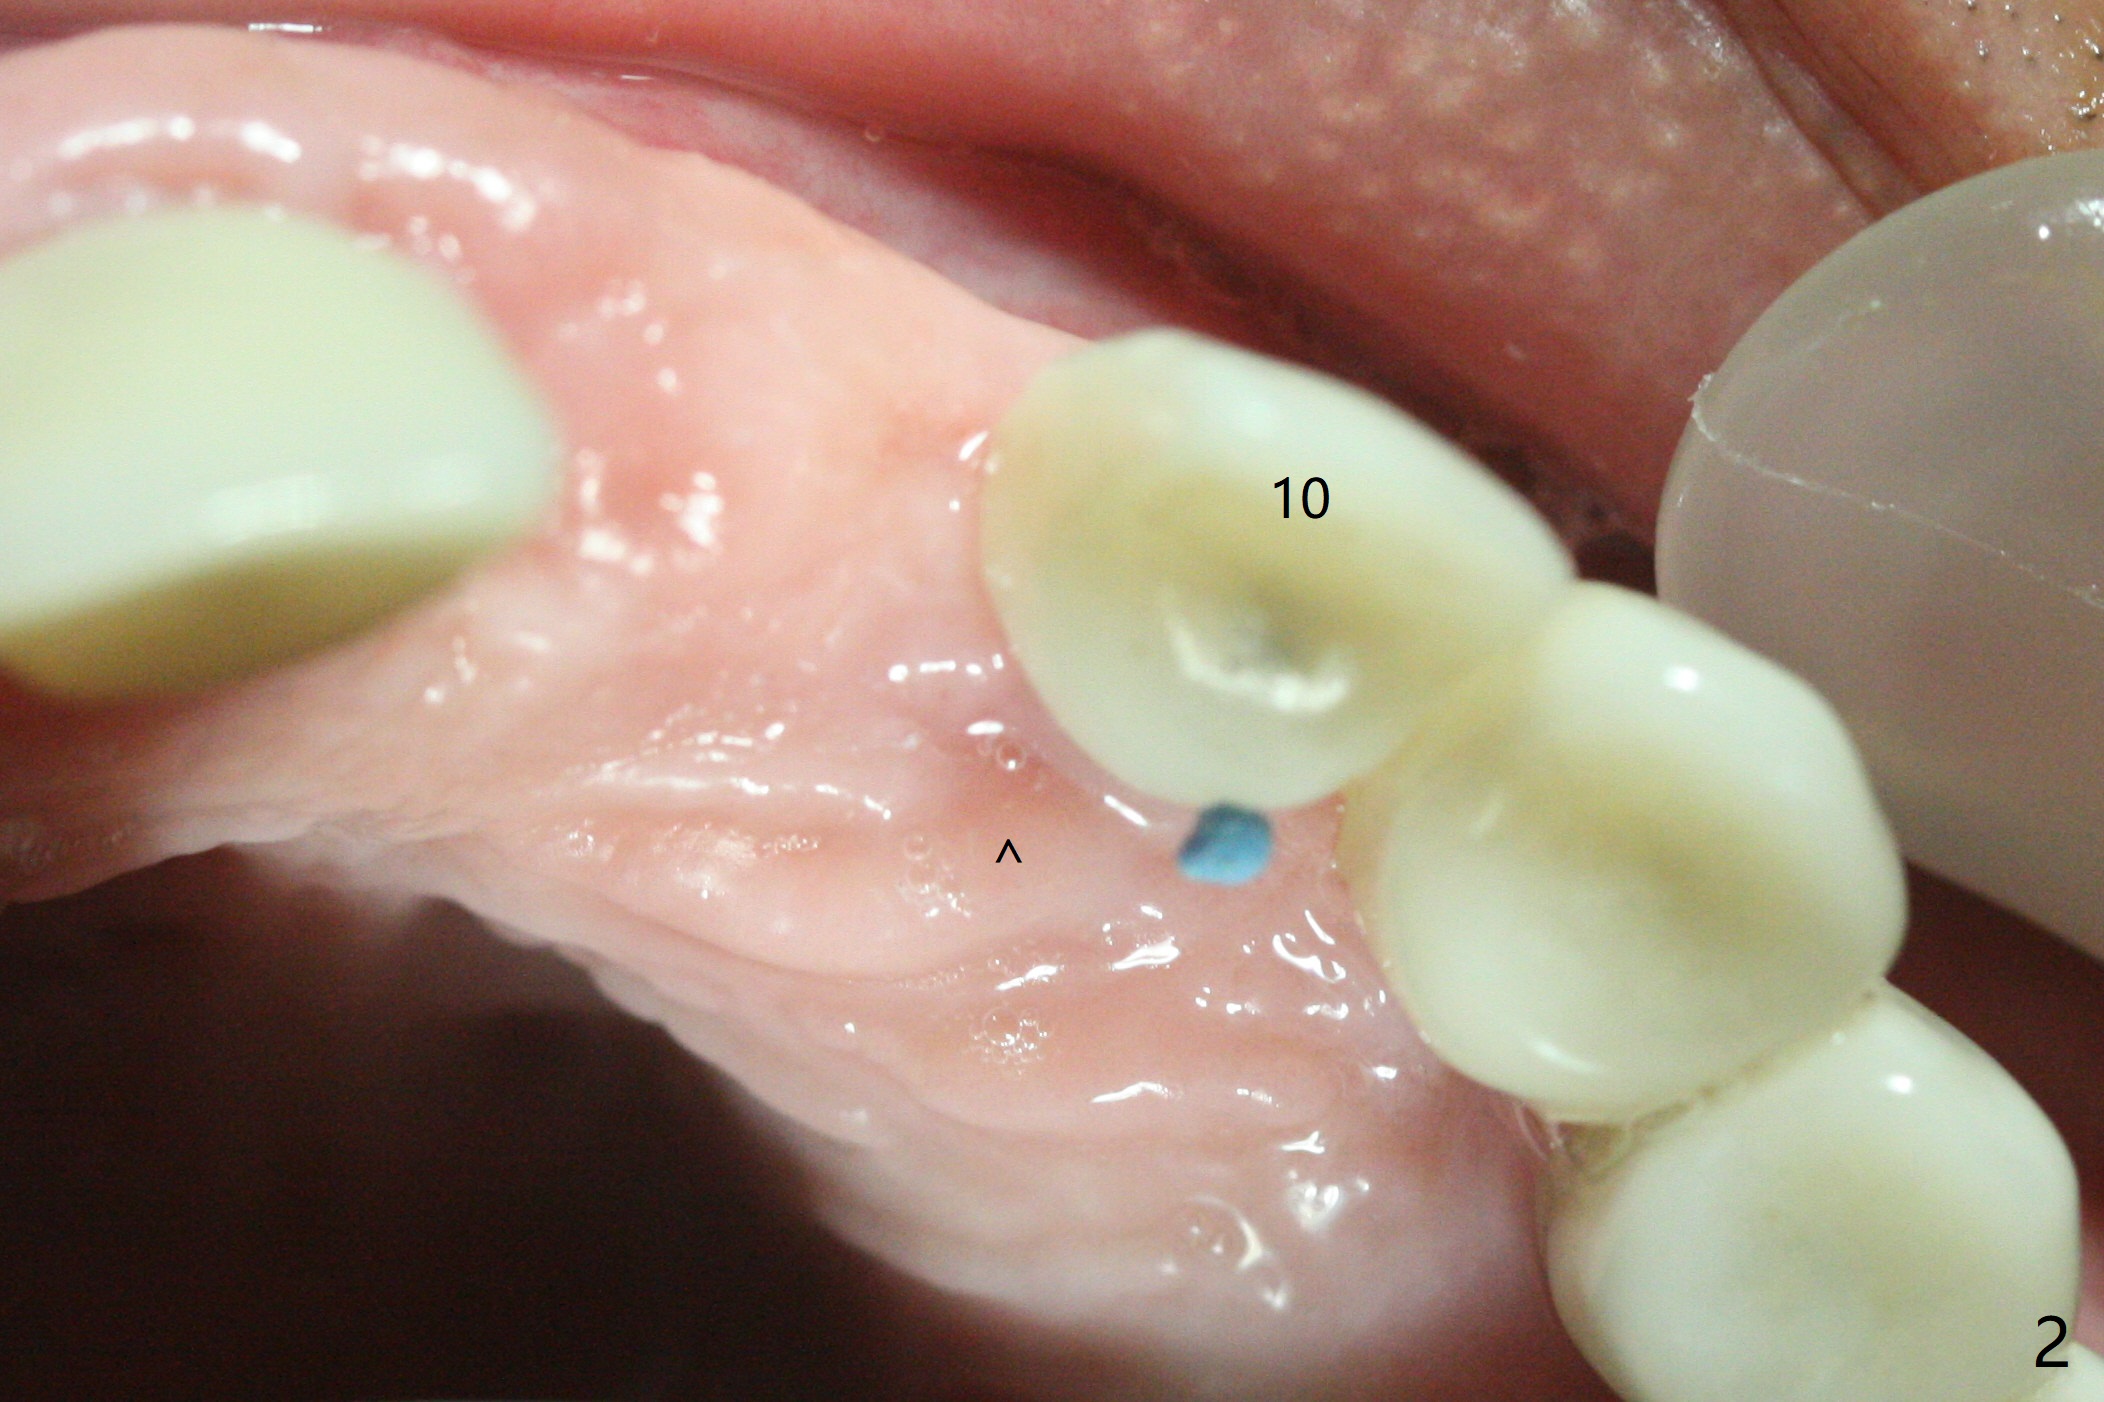

The implant access at #9 closes 1 week post implant fracture (Fig.1,4). There is mild gingival erythema at #10 (Fig.2,3 ^). There is bone around the fractured implant, which is palatally placed (Fig.5). The 2 mm implant is removed using 2/3 mm trephine bur. In spite of moving the osteotomy buccally, a 4.5x4 mm, 15 degree A-type angled abutment is installed for an immediate provisional following placement of a 3.5x10 mm implant (Fig.7, 25 Ncm). Sticky bone is placed (Fig.7 *) palatal to the implants at #9 and 10 (with thread exposure, Fig.6). While the majority of periodontal dressing remains in place (Fig.9,10), the suture in the exposed area appears to hold the papilla in place (Fig.8 <). Herpetic infection develops in the palate (Fig.9). Two months later, the gingiva at #10 is healthy; it appears that the implant threads are covered by bone graft. The immediate provisional (fabricated before suture) keeps the gingiva in an ideal position for impression of final restoration. It appears that the access hole is in a right area for screw retained restoration. The gingival cuff is healthy immediate pre-cementation, 4 months postop (Fig.12,13). The lab does not make access hole for the final crown (Fig.14). The implant remains subcrestal 4 months postop (Fig.15). Since the shade of the crown is off, the abutment remains un-torqued and the crown is cemented with temp bond. The implant threads at #10 seem to be covered by bone graft 4 months postop (Fig.16).